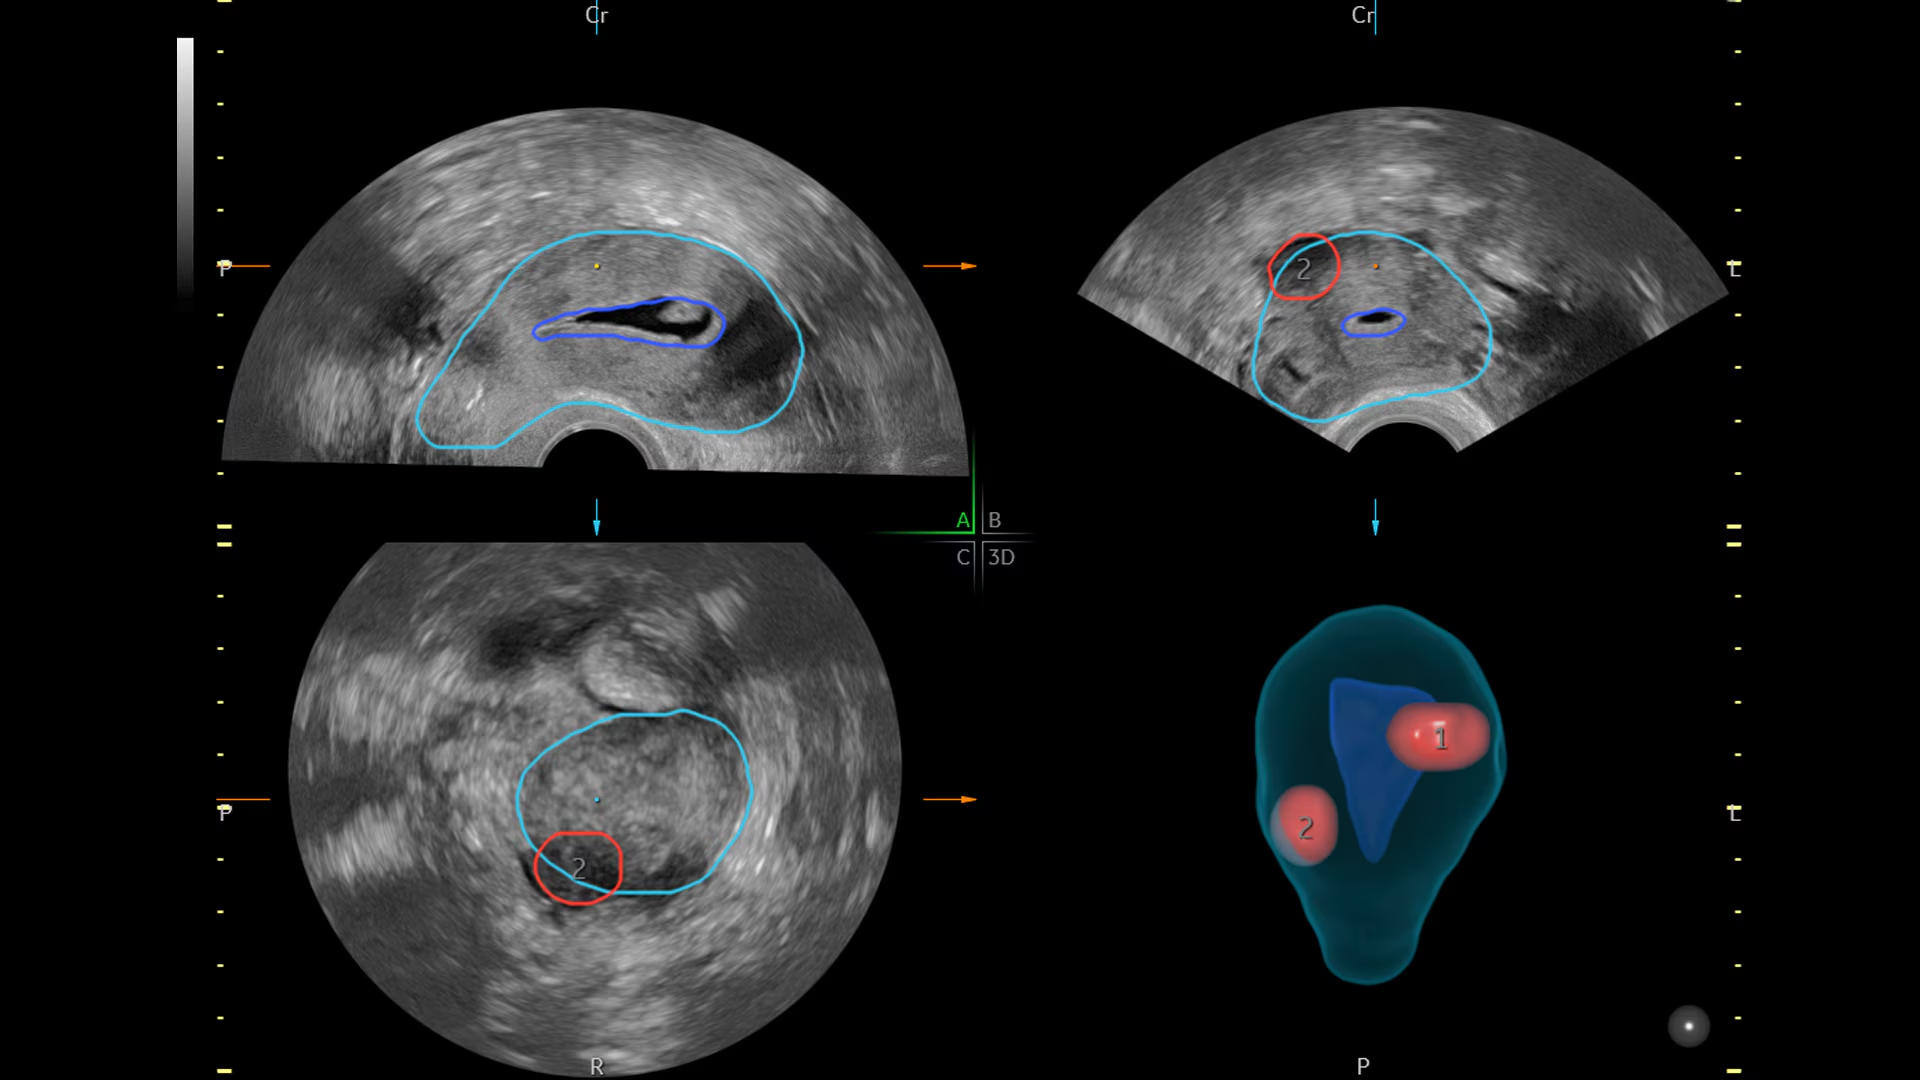

Для гинекологической практики доступны модули SonoGYN и Fibroid Mapping, которые автоматически формируют коронарные срезы матки и 3D-карту миоматозных узлов. Врач получает точные объёмы и пространственное расположение узлов для планирования терапии.

SonoGYN распознаёт контуры полости и миоматозных образований, создаёт их пространственную модель и позволяет оценить взаиморасположение узлов для планирования лечения и документирования